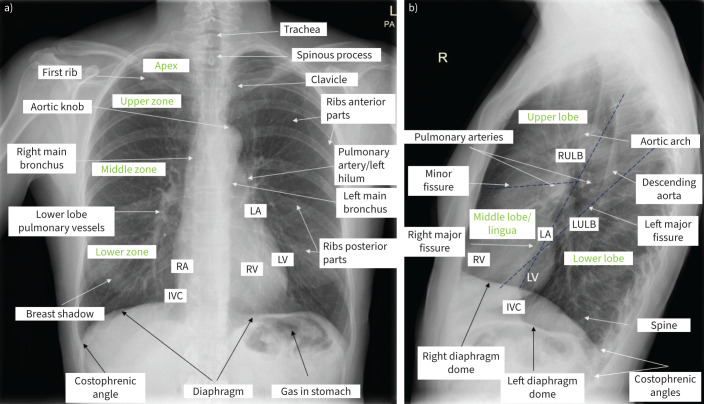

Imaging methods are fundamental tools to detect and diagnose lung diseases, monitor their treatment and detect possible complications. Each modality, starting from classical chest radiographs and computed tomography, as well as the ever more popular and easily available thoracic ultrasound, magnetic resonance imaging and nuclear medicine methods, and new techniques such as photon counting computed tomography, radiomics and application of artificial intelligence, has its strong and weak points, which we should be familiar with to properly choose between the methods and interpret their results. In this review, we present the indications, strengths and main limitations of methods for chest imaging.